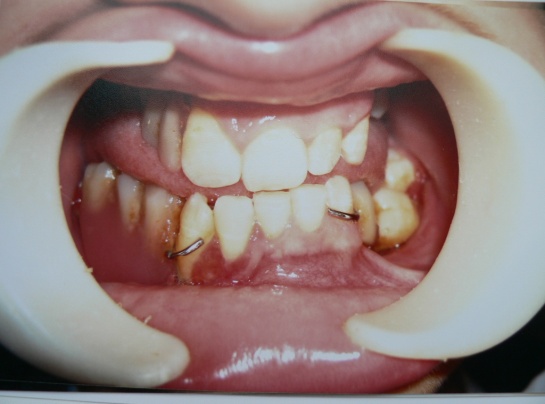

В настоящее время ребёнку проведено протезирование. Процесс в полости рта стабилизирован. Динамическое наблюдение проводится 3 раза в год совместно с хирургом и ортопедом. Клиническая картина до- и после лечения представлена на рис.